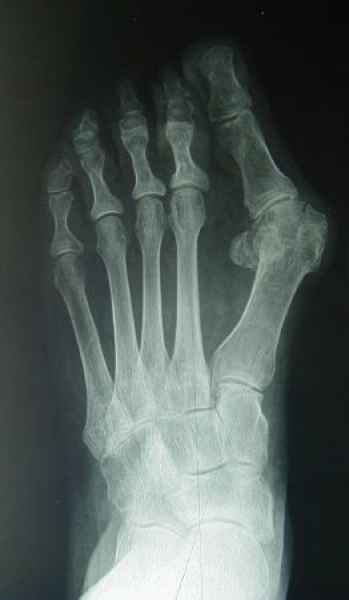

El pie es el órgano distintivo y característico de la especie humana, la única criatura que marcha erguida. El pie es una muy compleja estructura de arquitectura perfecta, adaptado a su función de apoyo, traslación, salto, con una riquísima sensibilidad que le permite detectar las más leves imperfecciones del suelo para estabilizar la marcha.

Tanto la estructura del pie como su funcionalismo que es la marcha, pueden ser asiento y manifestación respectivamente de alteraciones locales ó sistémicas, por lo que su cuidadoso examen resulta de extrema utilidad diagnóstica.